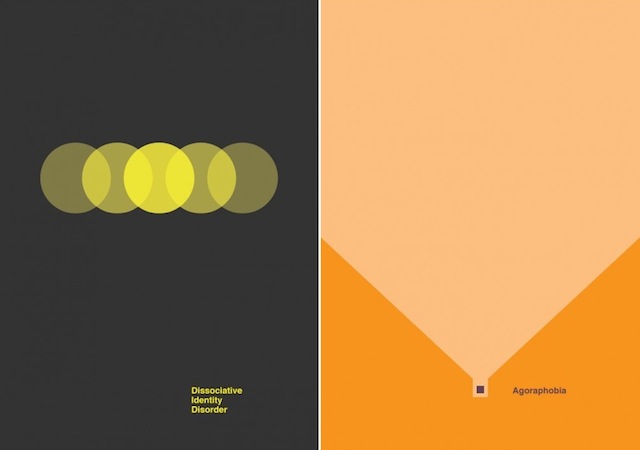

Like Christian Stoll who has put colors on psychology and emotions, Designer Patrick Smith managed to put graphic symbols on complex mental disorders. Through 7 minimalist posters and respecting precise color codes, we can decrypt the feelings of lack of understanding, division and isolation in certain psychological diseases.